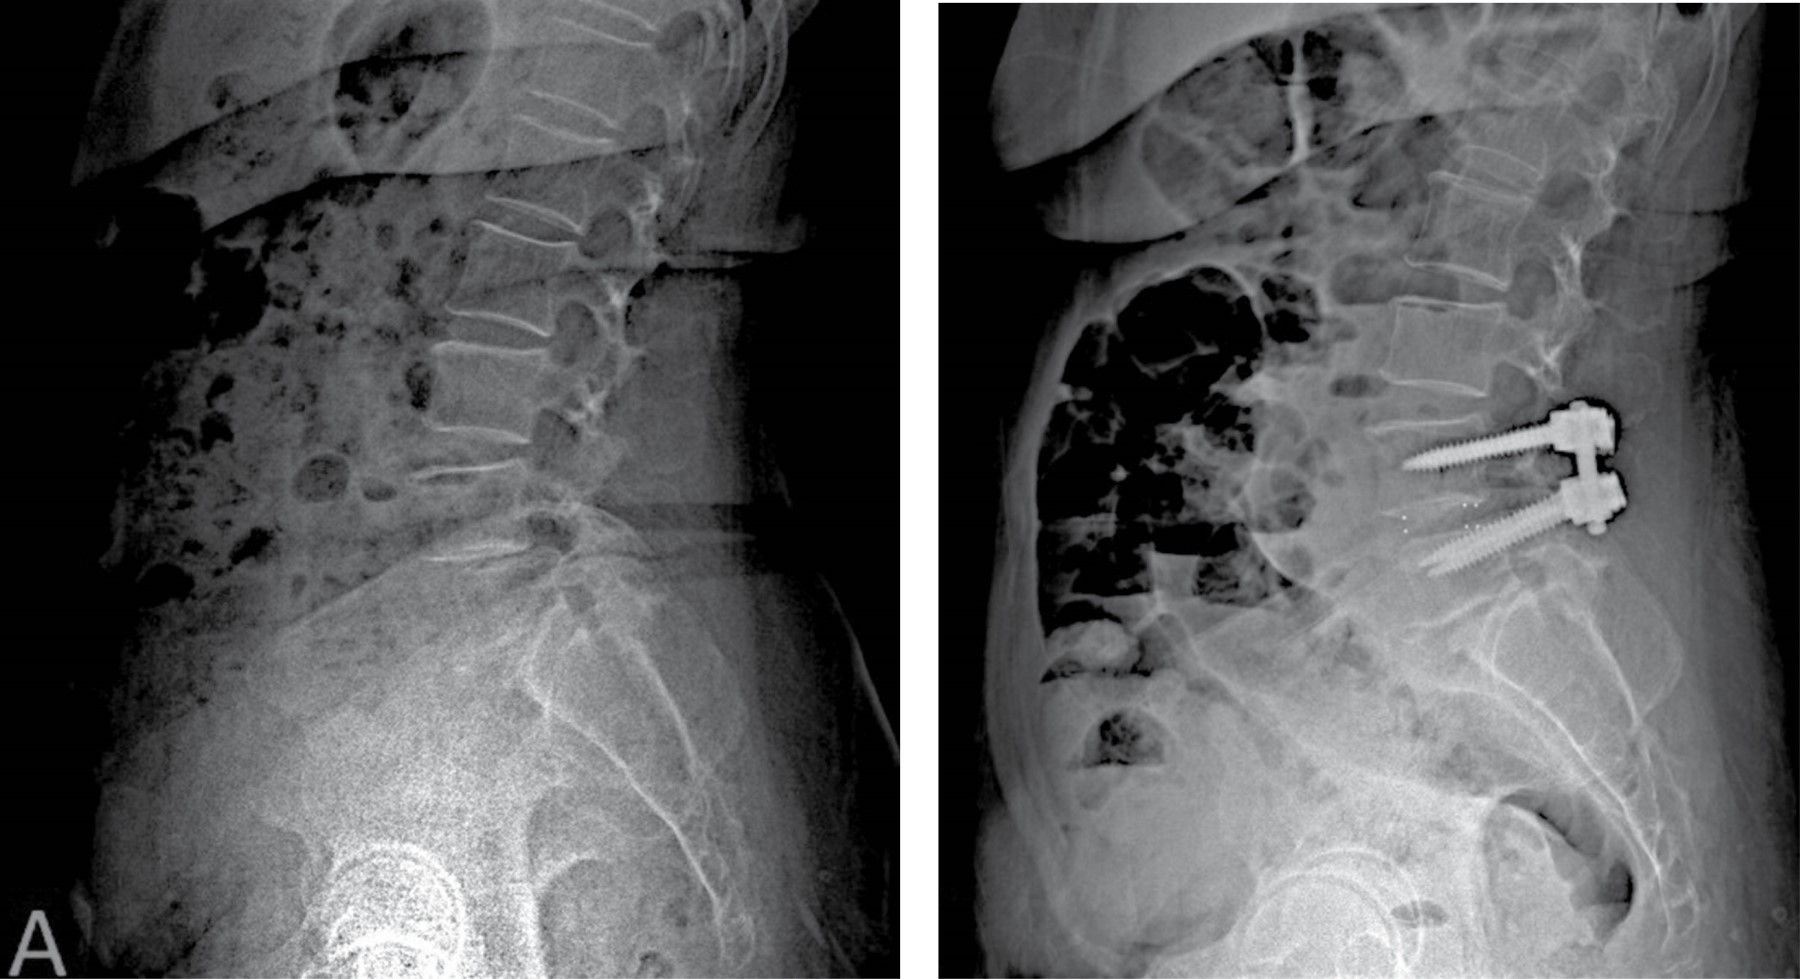

Norton et al. reported that patients undergoing interbody fusion through an anterior or lateral approach are significantly less likely to develop intraoperative blood loss anemia but present a higher risk of visceral injury compared to those who underwent PLIF/TLIF35 (Figure 2).

The addition of anterior column support or 360-degree fusion has many theoretical benefits. Authors propose that anterior spine support improves fusion rates by increasing the surface area available for fusion, offers indirect decompression, and helps restore normal lumbar lordosis. Intersomatic fusion has become a popular method in the treatment of spondylolisthesis, with used ranges from 14% in 1999 to 37% in 2011.49 There are several ways to achieve anterior support, each with its own benefits and a unique set of complications21 (Figure 3).